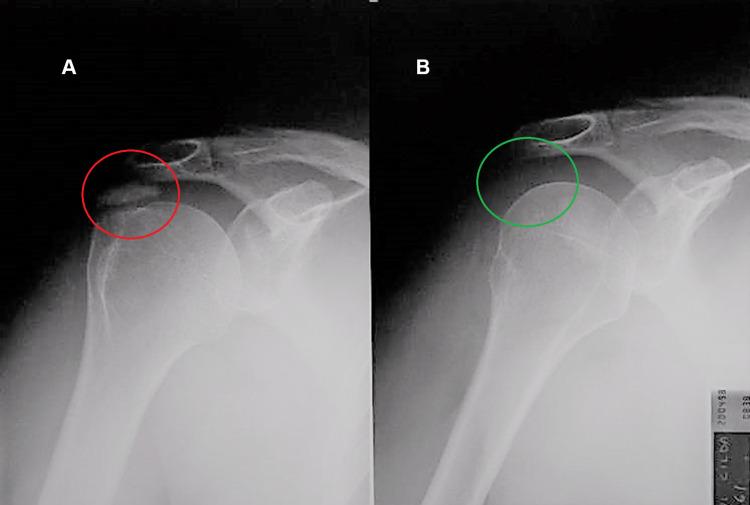

Calcific tendinitis of the shoulder (CTS) is one of the pathological conditions that most often affects the shoulder and consists of a calcium deposit that settles within the tendon tissue of the rotator cuff. The scientific literature has long highlighted the impact of anxiety, stress, and depression on CTS. The goal of this case report is to highlight how the emotional state of patients and their neuro-psychomotor behavior induce a state of constant muscular tension which, through the physical phenomenon of piezoelectricity, causes calcium salts to precipitate and form calcifications. Therefore, stress, anxiety, and depression are likely factors underlying the etiopathogenesis of CTS. Consistent with this interpretation, this report presents five cases of CTS treated with three specific neurobiological stimulation treatments using the radioelectric asymmetric conveyer (REAC) technology, which has demonstrated its effectiveness on alterations in postural attitude intended as neuro-psychomotor behavior, anxiety, stress, and depression, as well as on autonomic and metabolic alterations of the tissues at a local level. The results presented suggest that this approach may be useful in the treatment and prevention of CTS.

肩部钙化性肌腱炎(CTS)是最常影响肩部的病理状况之一,由沉积在肩袖肌腱组织内的钙沉积物组成。科学文献长期以来一直强调焦虑、压力和抑郁对CTS的影响。本病例报告的目的是强调患者的情绪状态及其神经心理运动行为如何诱发持续的肌肉紧张状态,这种状态通过压电物理现象导致钙盐沉淀并形成钙化。因此,压力、焦虑和抑郁可能是CTS发病机制的潜在因素。与这种解释一致,本报告介绍了五例CTS患者,采用三种特定的神经生物学刺激疗法进行治疗,使用无线电不对称输送器(REAC)技术,该技术已证明其对作为神经心理运动行为的姿势态度改变、焦虑、压力和抑郁以及局部组织的自主和代谢改变有效。所呈现的结果表明,这种方法可能对CTS的治疗和预防有用。